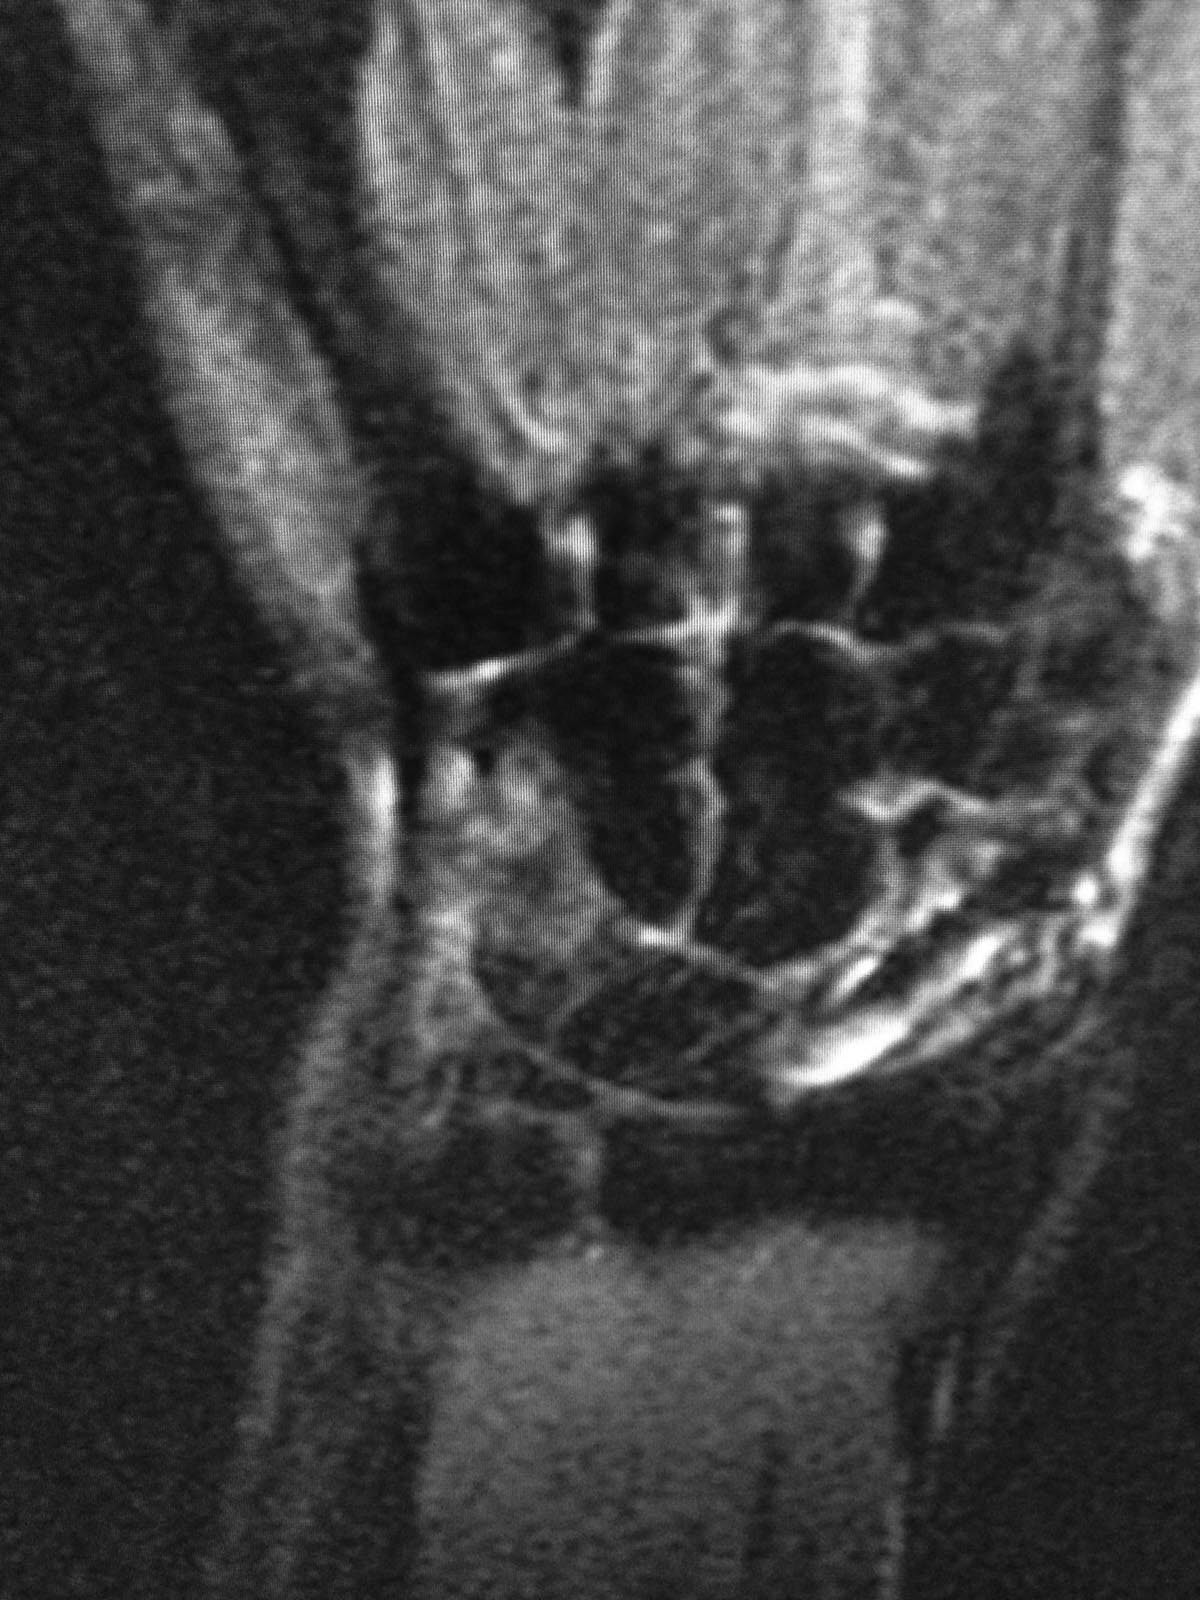

МОС винтом, в данное время в проекции ладьевидной кости болей нет, осевая нагрузка на 1ю пястную кость безболезненная, боли беспокоят при пальпации в проекции трехгранной кости и движениях в лучезапястном суставе(при пассивных и активных движениях возникают острые боли, так же в проекции трехгранной кости). На МРТ отмечаются проблемы в этой зоне. Со слов пациента, при периодических болях принимает таблетку найза, после чего все проходит.

Эльдар, по предоставленным срезам МРТ и описанной клинике сложно судить о состоянии связочного аппарата (в частности полулунно-трехгранной связки) и треугольного фиброзно-хрящевого комплекса (в частности суставного диска), повреждение которых могут давать описанные жалобы. Возможно, в описании МРТ что-то сказано об этом? Что можете сказать о тестах, выявляющих повреждение указанных образований? И все-таки боли возникают периодически или всегда сопровождают движения в кистевом суставе? Болит ли в покое? Андрей, Ваша логика совсем не ясна. Что общего между обсуждаемым пациентом и "стенозом лучевого запястного канала", кроме когда-то сломанной ладьевидной кости? Сергей, с хондроматозом тоже не ясно. Вы его видите на имеющихся снимках? Хондроматоз сустава - показание для удаления одной из образующих сустав костей? SAGo, в сообщении Эльдара нет указания на то, что болит больше всего по тыльной поверхности трехгранной кости.